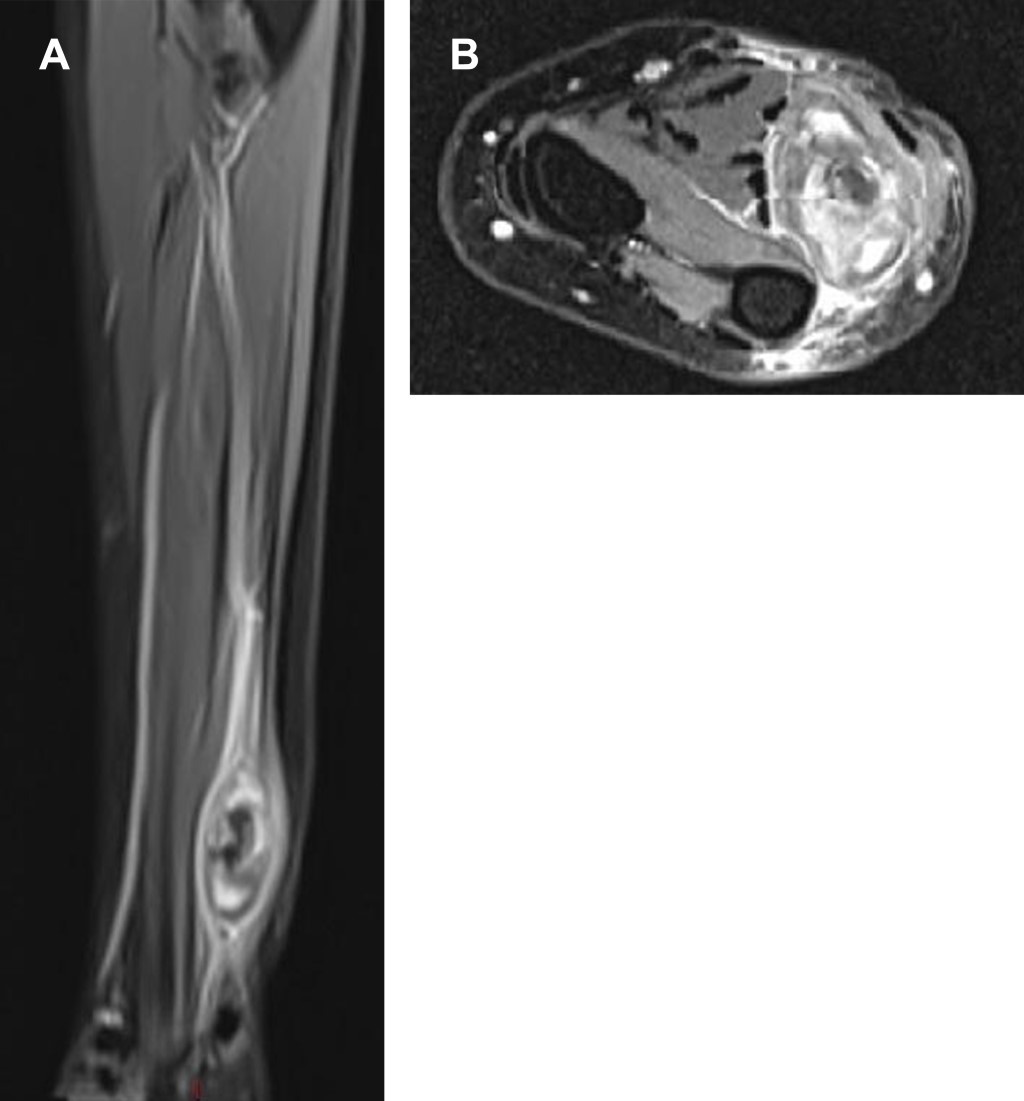

Los estudios de laboratorio no mostraron alteraciones. El ultrasonido reportó imagen nodular de 3.3 × 1.6 × 2.2 cm de morfología ovalada, bordes bien definidos, ecogenicidad heterogénea de predominio hipoecoica, desplazando en sentido caudal al nervio cubital y en sentido lateral a la arteria y vena cubital. Doppler a color muestra vascularidad periférica e interna de la lesión (Figura 1). La resonancia magnética ponderada de FAT SAT (saturación espectral) mostró imagen de aspecto sacular de contenido heterogéneo, el cual desplaza y comprime estructuras neurales y musculares adyacentes (Figura 2).

Figura 2